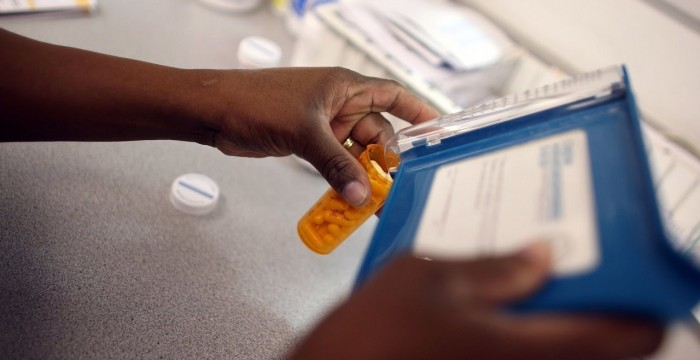

The trustees of the Social Security and Medicare funds said the costs of both programs are going to rise a lot more than the GDP.

Report: Medicare trust fund to dry up in 8 years